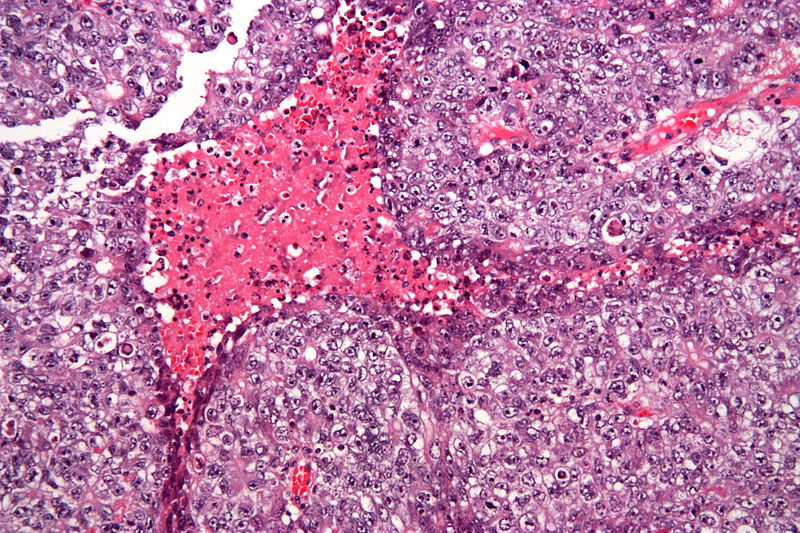

Dysgerminoma is the most common malignant germ cell tumor that is made up of big cells with oocyte-like central nuclei and transparent cytoplasm.